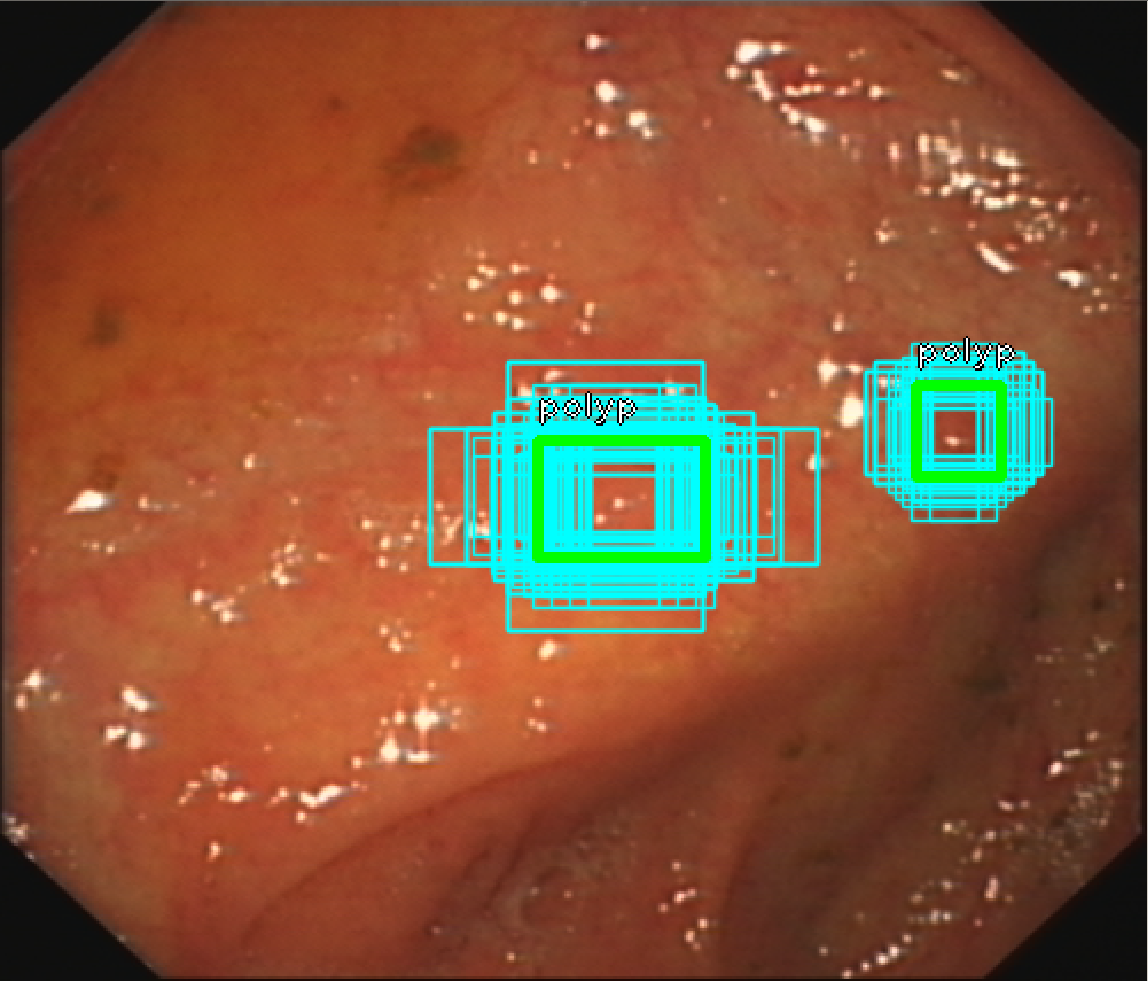

3.2 Anchor optimization

Anchors with different sizes and rations are generated on top of each pyramid level and feed into two subnets which are used to classify label and regress bounding box. Original anchor configurations uses sizes (32, 64, 128, 256, and 512) each size has three scales (20,213,223)superscript20superscript213superscript223(2^{0},2^{\frac{1}{3}},2^{\frac{2}{3}}) and three aspect ratios (1:2,1:1,2:1):121:12:1(1:2,1:1,2:1). As the quality of anchors will have direct impact on detection, keeping default anchor settings might not possible to detect multiple polyps smaller than 32 within a frame. In this regard, we use differential evolution algorithm Storn1997 to approximate optimal anchor configurations iteratively. Process of optimizing anchor configurations are detailed in Zlocha2019a , an object function which maximizes overlap area between anchor and object bounding box are optimized by a group of iteratively improved candidate solutions. We increase the number of anchors per level from 9 to 15 by having 5 aspect ratios so that each pyramid scale has denser anchor coverage. Unlike authors in Zlocha2019a all scales are optimized with their corresponding stride value associated. We use validation set to find optimal configurations, we eventually find the following anchor parameter combinations with scales(16 32 64 64 64)1632646464(16\>32\>64\>64\>64) and ratios (0.481 0.741 1.0 1.349 2.078)0.4810.7411.01.3492.078(0.481\>0.741\>1.0\>1.349\>2.078) fit our task best.

The figure 4 depicts the effect of anchor optimization. All boxes are centering at the object, after applying the optimized anchor parameters, each objects are associated with more boxes which also cover more area of polyps. The effects of having anchors like that is boxes are more likely to fit shapes that

Refer to caption

(a) sparse anchor coverage

(b) dense anchor coverage

Figure 4: example of anchor optimization. Anchor boxes on the left are the result of optimization, the ratio and sizes offer better coverage with GT label and more boxes are used.